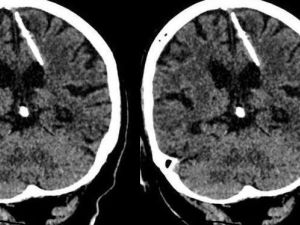

اكتشاف إبرة طولها 3 سم موجودة في دماغ امرأة روسية منذ 80 عاماً